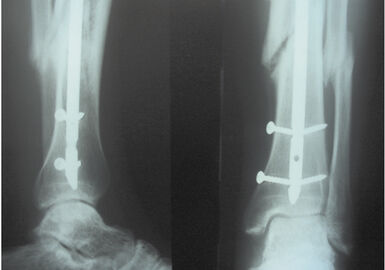

Аппарат Илизарова: принцип работы и применение